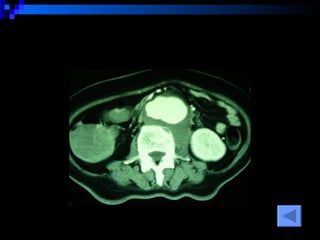

CT SCAN AAA juxtrareal -> bifurcation  Size 10*8*4 cm Inflamatory tissue  around AAA Intact renal artery Aortic dissection at juxtra renal -> bifurcation Bowel wall thickening at 3 rd -4 th  part of duodenum

CT SCAN AAAjuxtrareal -> bifurcation Size 10*8*4 cm Inflamatory tissue around AAA Intact renal artery Aortic dissection at juxtra renal -> bifurcation Bowel wall thickening at 3 rd -4 th part of duodenum